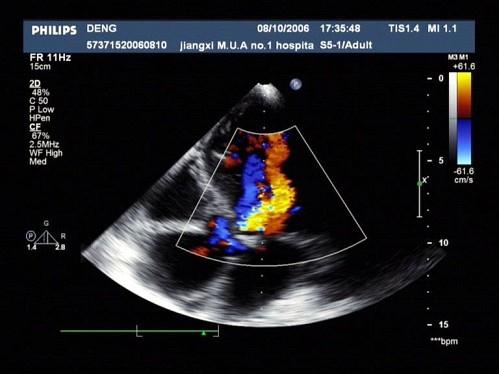

问题 患者,男,50岁,发热半月余,全身不适,乏力,食欲不振。根据超声心动图,最可能的诊断是?(?)

选项 A.风湿性心脏病 B.感染性心内膜炎 C.老年退行改变 D.主动脉瓣狭窄 E.冠心

答案 B